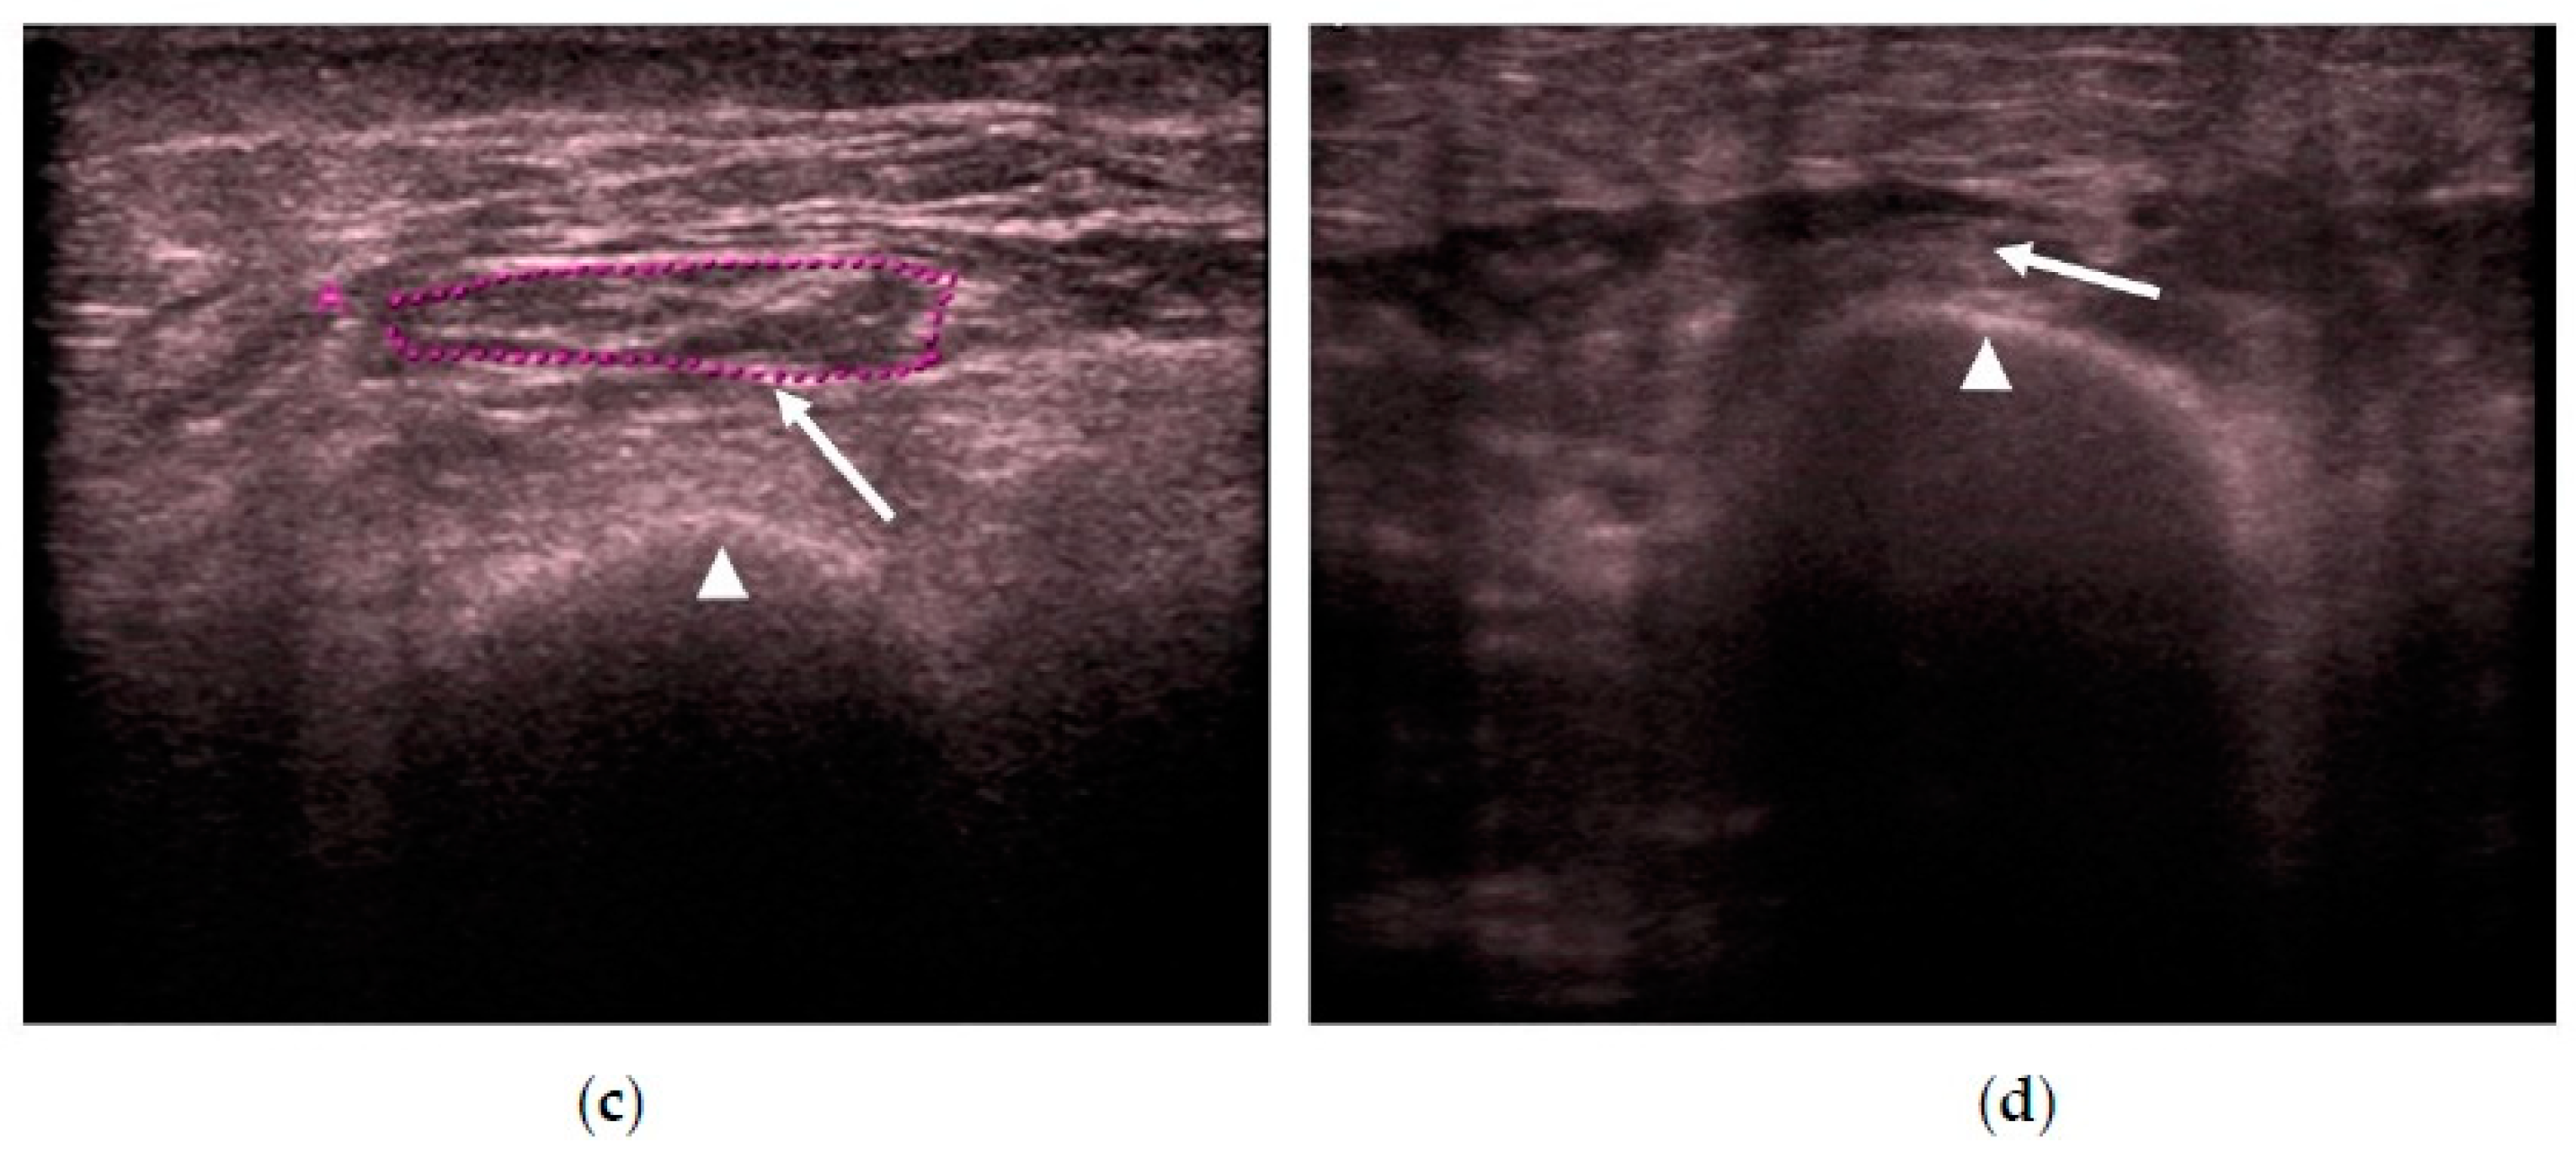

We measured the CSA in cm2 and muscle thickness in mm, and scanned for the presence or absence of edema in the subcutaneous cellular tissue and the intramuscular and intrafascial fluid (Figure 2).

Figure 2.

(a) Transversal QRF muscle US scan: multiorgan failure, tendon thickness of 2.6 mm (arrow), and femur (arrowhead). (b) Transversal QRF muscle US scan: multiorgan failure, cross-sectional area (CSA) of 0.89 cm2 (arrow), and femur (arrowhead). (c) Longitudinal QRF muscle US scan: muscle thickness of 7.1 mm (arrow) and femur (arrowhead). (d) Longitudinal QRF muscle US scan: subcutaneous edema, with intramuscular and interfacial fluid (arrowhead). QRF tendon is 1.5 mm (arrow) with the femur (thick arrow). QRF: quadriceps rectus femoris, US: ultrasound, CSA: cross-sectional area.